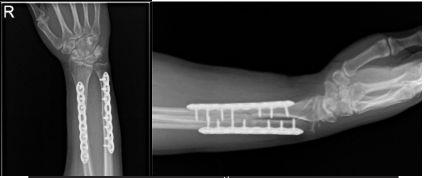

Right Forearm X-ray-32nd week post-operative

Long-arm splint was applied using Ace wrap. The patient was extubated and moved to recovery in a stable condition. From the 1st week to 36th weeks, we monitored the progress of patients by doing regular X Ray. And it showed significant changes from patient condition.

With consistent follow up visits, patients get well easily from his surgery. The patient tolerated activities and returned to his normal routine.